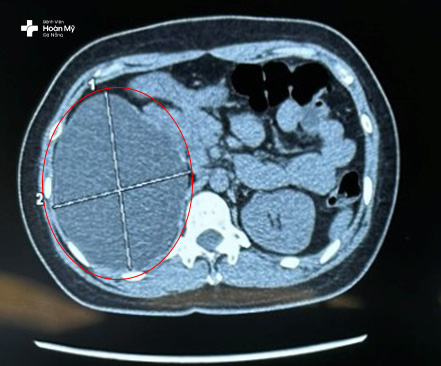

Hình ảnh nang thận lớn quan sát rõ trên hình chụp cắt lớp CT

“Kết quả cận lâm sàng cho thấy người bệnh có nang phải kích thước 120x101mm, nang lớn, nằm ở vị trí cực trên, chèn ép mô thận gây đau. Nang thận chèn ép lâu ngày có thể gây ảnh hưởng đến chức năng thận, cắt bỏ nang thận bằng phẫu thuật nội soi là phương pháp điều trị an toàn và hiệu quả nhất cho người bệnh lúc này” - Bác sĩ Bùi Quốc Triệu – Trưởng khoa Ngoại Tiết Niệu – Nam khoa nói.